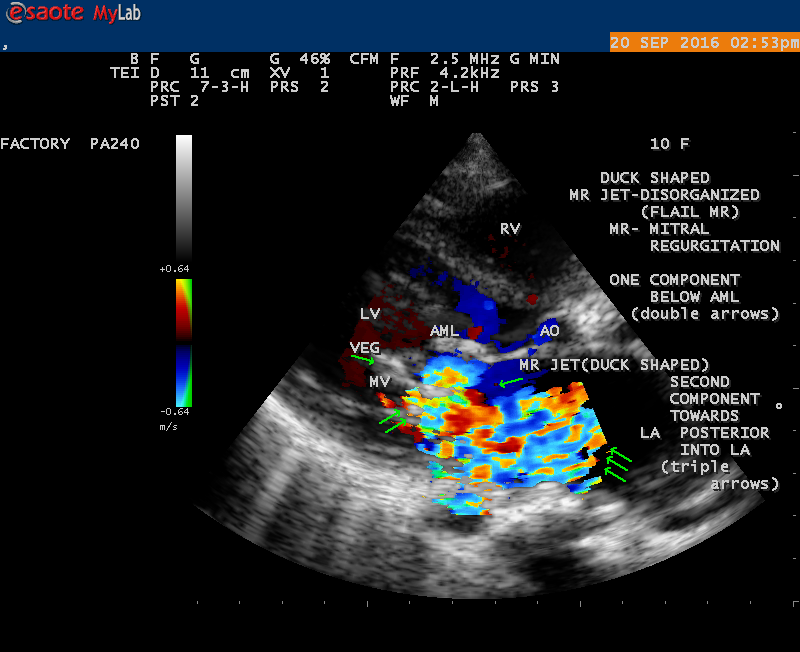

The most common and direct evidence of infective endocarditis is the vegetation and it begins as a microscopic focus of infection and gradually grows into a conspicuous mass. It is typically an irregularly shaped, highly mobile, echogenic mass attached to the free edge of a valve leaflet ( most commonly at the coaptation line) and tends to develop on the ‘upstream’ side of the valve leaflets ( ie, the ventricular side of aortic valve and the atrial side of mitral and tricuspid valves. They may be seesile or pedunculated, but usually has an oscillating or fluttering motion, a typical feature of most vegetations. Vegetation move with the leaflet in a more chaotic (‘oscillating’) manner and it may prolapse through the valve into the LV (left ventricle) as it opens as shown in Figures 3, 4 and 16 and into LA (left atrium) as it closing (Figure 5 and 6) . The mass of vegetation is typically homogeneous with echogenicity similar to that of the myocardium. The infectious process often alter the valvular structure and function. Extensive involvement of the leaflet may result in chordal rupture, leading to severe regurgitation as shown in Figure 21 . Direct and typical signs of RMCT (ruptured mitral chordate tendineae) were chain-flail or whiplash-like changes and had an incidence of 86.7%, causing severe regurgitation and mitral chordal rupture is the leading cause of flail mitral leaflet[30]. A large vegetation may obstruct the valve orifice as shown in Figure 1 and 2 , sometimes termed as “obstructive-type bacterial endocarditis” and producing a functional valve stenosis ( Ping-Pong mitral stenosis [31]) similar to left atrial myxoma as shown in Figure 29.

The shape of vegetation varies in this child as ‘popcorn’ like (Figures 1,3 and 4 ), rod-shaped (Figure ), basket shaped (Figure 7 )[33-Figure 13.3], ‘baby in hand’ appearance (Figure 18), ‘cucumber shaped (Figure 2 ) and a ‘bunch of plantain’appearance (Figure 33 ), ring shaped (Figure 19 }, bileaflet structure (Figure 9 )with bileaflet MR jet as shown in Figure 10 . and kissing forms (Figure 13 - parasternal long axis view, Figure 14 - apical four chamber view and Figure 15 - short axis view)

‘Flail’ Mitral Regurgitation (MR)

The anatomic disruption of a portion of the mitral valve apparatus dueto the underlying rheumatic valvulitis with predisposing infective endocarditis which form a vegetation , resulting an eccentric regurgitation jet with orientation opposite in direction of the leaflet having the anatomic defect such as ‘flail’. In the presence of ‘flail leaflet’, the mitral regurgitant spectral signal may have an atypical appearance and the flail portion oscillate in the spectral signal of regurgitant flow stream to produce a ‘tiger stripe’ appearance as shown in Figure 27. associated with ‘whistling’ sound on auscultation[33-Figure 11.85]. The mitral regurgitation (flail MR) jet is chaotic as shown in Figure 26, highly eccentric (Figure 22) and disorganized with one component behind the anterior mitral leaflet and the second component directed towards posterior immediately as in Figure 21 [33- Figure 11.79].